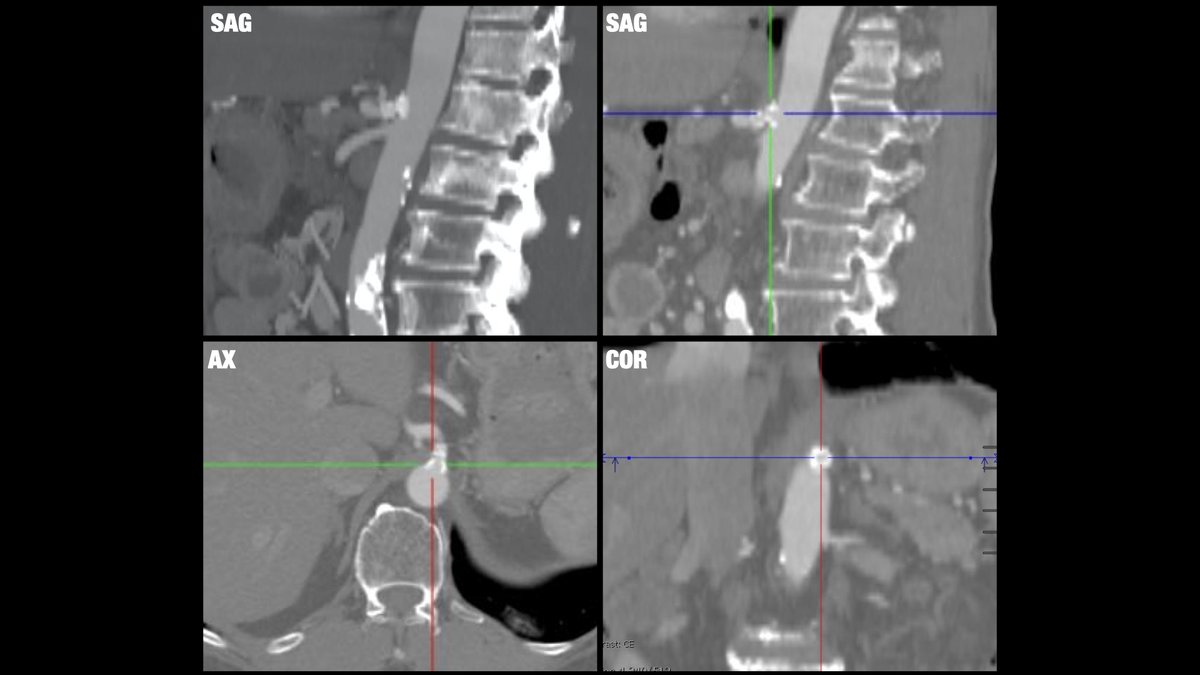

Median arcuate ligament (or celiac artery compression) syndrome, rare condition leading to upper abdominal pain due to vascular compression, treated with endovascular stent here. Brigham and Women's Radiology @AURtweet FOAMrad SAR Resident and Fellow Section Future Radiology Residents Harvard Macy CBR #MedEd

Median arcuate ligament (or celiac artery compression) syndrome, rare condition leading to upper abdominal pain due to vascular compression, treated with endovascular stent here. <a href="/BrighamRad/">Brigham and Women's Radiology</a> @AURtweet <a href="/FOAMrad/">FOAMrad</a> <a href="/SAR_RFS/">SAR Resident and Fellow Section</a> <a href="/futureradres/">Future Radiology Residents</a> <a href="/HarvardMacy/">Harvard Macy</a> <a href="/CBRadiologia/">CBR</a> #MedEd